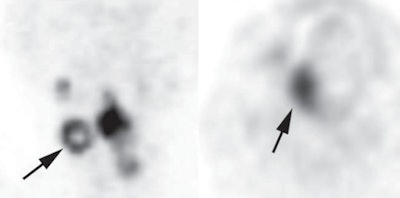

Of the parameters, the strongest predictor was a qualitative one, ring-shaped FDG uptake, according to lead author Dr. Sho Koyasu, from the department of diagnostic imaging and nuclear at medicine at Kyoto University Graduate School of Medicine, and colleagues (AJR, April 2014, Vol. 202:4, pp. 851-858).

As good as these quantitative factors were, the shape of FDG uptake was better. Patients with sphere-shaped patterns of FDG uptake were almost 19 times more likely to survive than those with ring-shaped patterns (hazard ratio = 18.92).

Of the 108 patients, 14 had ring-shaped patterns and 94 had sphere-shaped patterns. Approximately 90% of those with sphere-shaped patterns survived for more than six years. In comparison, 10% of subjects with ring-shaped patterns survived for more than 36 months.

"Our findings suggest that the uptake pattern on FDG-PET/CT can provide better prognostic information than conventional quantitative patterns," the authors wrote. This could be because uptake patterns better reflect intratumoral necrosis or heterogeneous morphology, they added.